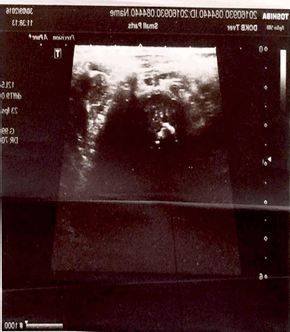

Ультразвуковая диагностика проводилась всем пациентам с МЭО (n=97; 100%), в дебюте заболевания выполнена у 29 детей (29,89%). Методика высоковерифицируема во время операции. Чувствительность метода - 92,5%, специфичность - 84,6%, точность - 91,04%. Определялись следующие эхографические признаки: увеличение толщины мягкотканых структур, скопление жидкости вокруг сустава, со стороны полости сустава наблюдались утолщение капсулы, присутствие внутрисуставной жидкости; изменения структуры эпифизарного хряща, формы и структуры ядра, окостенения эпифиза, изменения эхогенности зоны метаэпифиза, размытость ее границ, гиперэхогенность надкостницы и ее утолщение, нарушение границ наружного контура. Изменения в метаэпифизарной зоне - основной эхографический признак МЭО - регистрировались на 4-7-й день болезни. У пациентов в интрамедуллярной фазе обнаружены: отек параоссальных мягких тканей (n=15; 51%), утолщение капсулы сустава (n=10; 34%), жидкость в полости сустава (n=11; 37%). В экстрамедуллярной фазе на 4-7-й день МЭО: изменения эпифизарного хряща в виде участков повышенной эхогенности (n=31; 64%), нечеткость контура метафиза (n=35, 72%), утолщение надкостницы (n=26; 51%) (рис. 2).

Рис. 2. Сонограммы левой бедренной кости. УЗ-картина деструктивного процесса